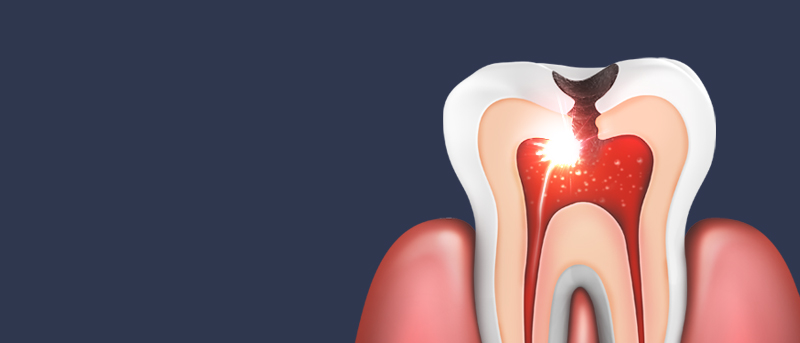

잇몸 전체가 무너져 동시다발적으로 죽어가던 치아들을 한꺼번에 살려 냅니다.